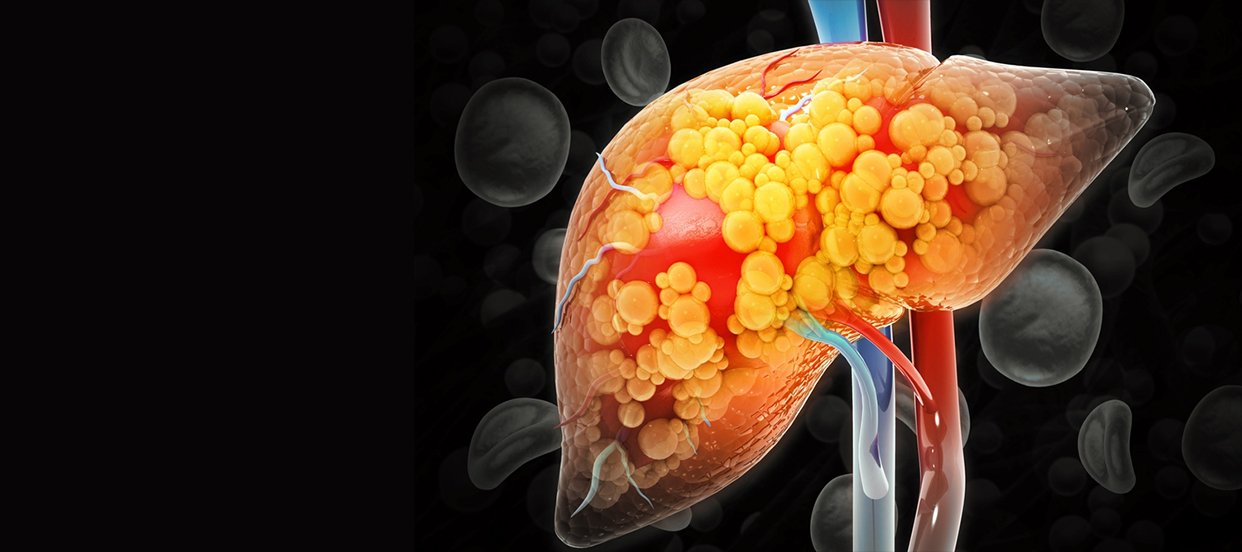

Banyak orang langsung panik saat mendengar diagnosis fatty liver. Padahal, pertanyaan gangguan fatty liver bisa pulih dengan cara apa justru membuka peluang besar untuk memperbaiki kondisi tubuh.

Hati memiliki kemampuan pulih yang sangat baik jika Anda memberi dukungan yang tepat. Selama kerusakan belum terlalu jauh, liver masih bisa membersihkan lemak secara bertahap.

Saat membahas gangguan fatty liver bisa pulih dengan cara apa, pola makan selalu berada di urutan pertama. Sebagian besar kasus fatty liver muncul akibat kelebihan gula dan karbohidrat olahan.

Ketika asupan gula berlebih masuk ke tubuh, hati mengubahnya menjadi lemak. Jika kondisi ini terus berulang, lemak akan menumpuk di dalam sel hati.